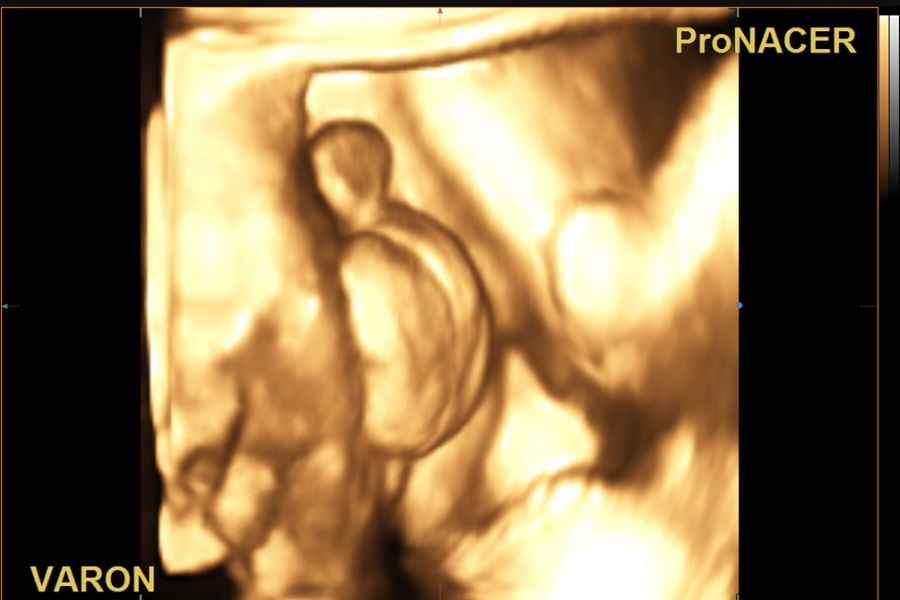

Ecografía 4D